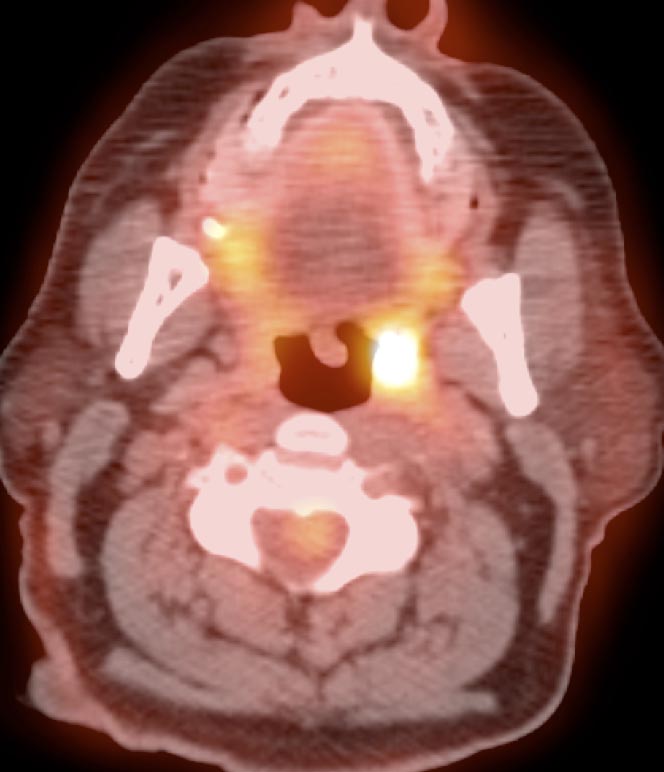

Palatine Tonsils

The palatine tonsils frequently demonstrate very intense metabolic activity.

Interpretation of tonsillar uptake is depends on the clinical presentation of the patient, the degree of FDG uptake, the size of the tonsils and the bilateral or unilateral nature of the findings.

- Bilateral and fairly symmetric FDG-uptake in non-enlarged palatine tonsils is almost always a normal finding.

- Bilateral and fairly symmetric FDG-uptake in enlarged palatine tonsils is nearly always inflammatory in nature (although can occasionally be seen with lymphoma).

- Unilateral or asymmetric increased FDG uptake within one palatine tonsil warrants careful and detailed assessment (addressed in detail, here).